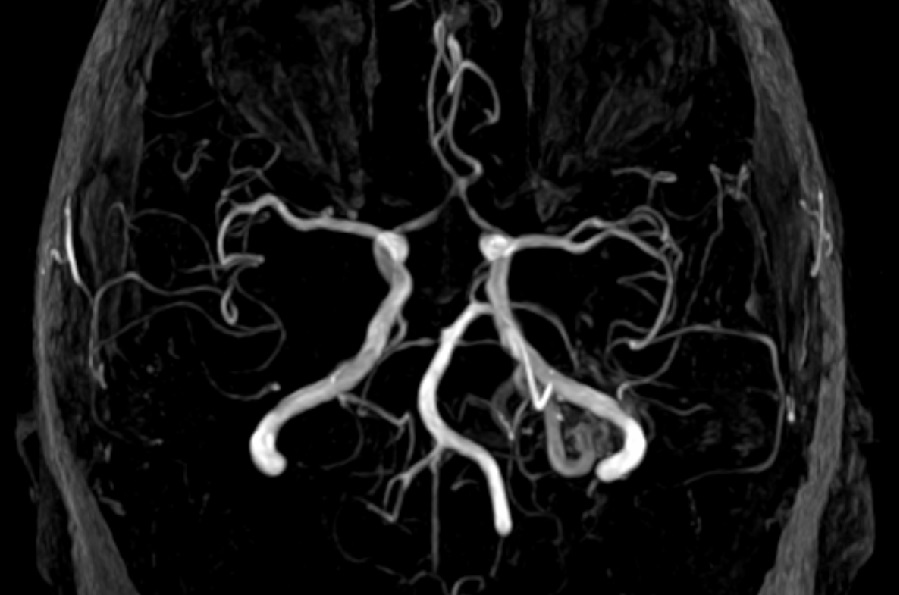

malformacia.jpgЦеребральной аневризмой называют мешковидное выпячивание стенки сосуда головного мозга, которое ведет к риску разрыва и внутричерепного кровоизлияния (геморрагический инсульт). Большинство разрывов происходит в пространстве между веществом головного мозга и тонкой тканью покрывающей мозг, «мягкой мозговой оболочкой». Такой тип инсульта называется «субарахноидальное кровоизлияние».

Разрыв аневризмы - угрожающее жизни состояние, требующее немедленного медицинского вмешательства.  В случаях, когда неприменим метод эндоваскулярной эмболизации используется метод клипирования аневризмы, позволяющий предупредить разрыв. Целью клипирования является исключение аневризмы из нормального кровотока с сохранением мелких сопутствующих здоровых ветвей.